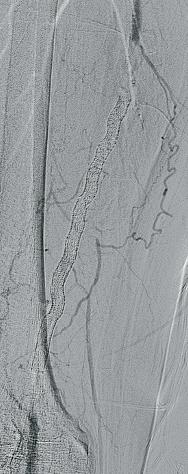

1. CTO of the left superficial femoral artery in a male patient suffering from severe claudication in the left calf

2. After subintimal passage, it was impossible to redirect the guidewire into the patent lumen distal to the CTO

3. Positioning of the BeBack catheter to re-enter the guidewire. Arrow indicates an orientation-marker

4. Marker appearing as a “C” indicates the direction of the needle, with the needle protruding maximally out of the BeBack catheter

5. An 0.018” guidewire passing into the patent distal lumen

6. Result after stenting